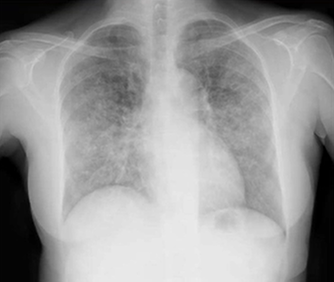

29歳男性。2週間前から左側腹部痛が出現し、改善を認めないため救急外来を受診した。 6ヵ月前からHIVと非薬剤耐性の肺結核の診断を受けており、抗レトロウイルス薬…